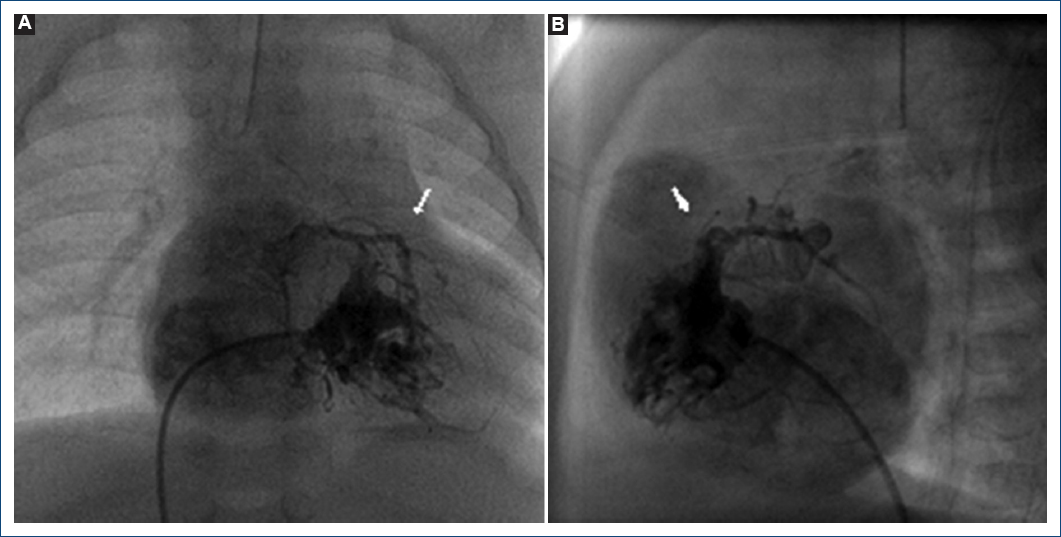

Paciente de sexo femenino de dos meses de edad, peso 3,335 g, talla 49 cm. Cianosis desde el nacimiento, hospitalizada a los 13 días por desaturación que mejoraba parcialmente con oxígeno. ECOTT: AP-SVI, motivo de referencia a nuestra institución. Exploración física: cianosis ++, saturación de oxígeno (SaO2) 77%, soplo continuo en foco pulmonar grado III/IV. Se confirma el diagnóstico de AP-SVI además de CVC, comunicación interauricular (CIA) restrictiva y conducto arterioso permeable (CAP) con extremo pulmonar de 2.5 mm. Se realizó cateterismo cardiaco donde se observó un VD tripartita con CVC y estenosis crítica en el tercio proximal de la descendente anterior (DA) con flujo retrógrado en sístole (Figs. 1 y 2). Se catalogó como CCVDC y el plan terapéutico paliativo fue: atrioseptostomía con balón más colocación de un stent coronario no medicado de 4 x 16 mm en el conducto arterioso. A las 8 horas del procedimiento presentó deterioro hemodinámico progresivo, acidosis metabólica, se inició apoyo inotrópico, el EKG demostró infarto extenso del ventrículo izquierdo (VI) (Figs. 3 y 4). ECOTT con hipomotilidad grave del VI y del septum interventricular, evolucionó con choque cardiogénico refractario, bradicardia grave y asistolia, se realizaron maniobras avanzadas de reanimación sin respuesta. No se autorizó estudio post mortem.

Figura 1 Ventriculografía derecha. Se observa atresia pulmonar con septum ventricular íntegro con conexiones ventrículo-coronarias, estenosis grave en el tercio proximal de la descendente anterior (flecha). A: proyección postero-anterior. B: proyección lateral izquierda.

Figura 2 Coronariografía izquierda. Se observa dilatación del tronco coronario izquierdo y estenosis crítica en el tercio proximal de la descendente anterior y las conexiones ventrículo-coronarias (flecha). A: proyección cuatro cámaras. B: proyección oblicua anterior derecha.